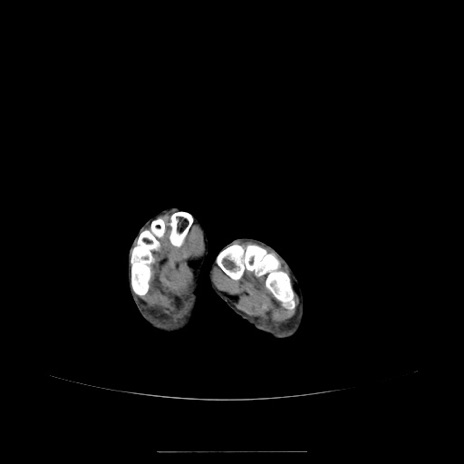

冠状断像

【症例】70歳代女性

【主訴】お腹が張る

【現病歴】1週間くらい前から腹部膨満の自覚あり。昨日夜から増悪したため、本日救急外来受診。

【身体所見】意識清明、BT 36.5℃、BP 165/106mmHg、HR 80bpm、SpO2 98%、腹部:膨満、軟、自発痛・圧痛なし、触診にて不快感あり、腸蠕動音:減弱

【データ】WBC 12600、CRP 1.04